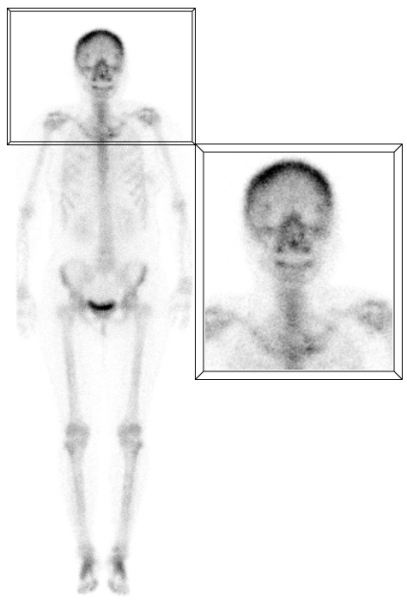

A) Captación difusa en huesos frontales

La hipercaptación difusa y simétrica en los huesos frontales suele ser secundaria a hiperostosis, definida como un crecimiento benigno excesivo de la tabla interna de los huesos frontales y, en algunos casos, parietales. Aunque se creía relacionada con trastornos hormonales, actualmente su etiología no está completamente clara. Se presenta en el 5 - 12% de la población, siendo más común en mujeres adultas mayores. Suele ser un hallazgo incidental sin significado patológico, aunque puede estar asociado a condiciones como diabetes, enfermedad tiroidea, virilismo y acromegalia, entre otras(1,2) (fig. 1).